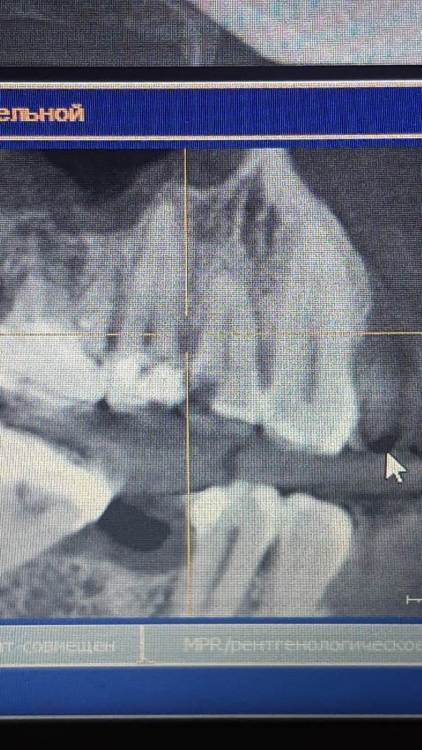

Ankauragan Опубликовано 12 декабря, 2023 Поделиться Опубликовано 12 декабря, 2023 Над 6 ой верх слева (на фото справа) - стал появляться исчезать 2 раза в этом месяце свищ, на снимке видно разрежение, можно ли вылечить или удаление?? Ссылка на комментарий

DoctorT Опубликовано 13 декабря, 2023 Поделиться Опубликовано 13 декабря, 2023 48 минут назад, Ankauragan сказал: Это я тоже прочла) про отток , Можно не удалять зуб? Видно по снимку разряжение это фатальное или попробовать лечить? мой совет - удалять. Состояние самого зуба (изменен в цвете , на 90% выполнен пломбой, разряжение в области расхождения корней, скорее всего есть подвижность) весьма плачевное. 2 Ссылка на комментарий